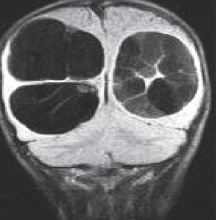

МРТ головного мозга. Т1-взвешенные корональная и сагиттальная МРТ. Эпидермоидная киста левой височной доли.